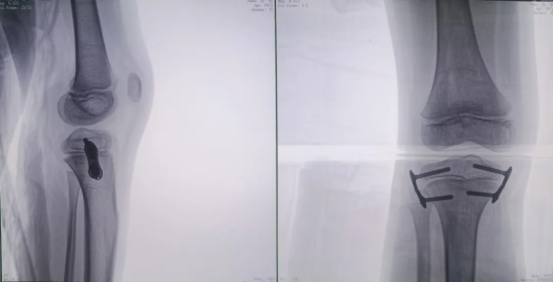

Preoperative Imaging

During the procedure, the positioning guidewire is inserted into the growth plate. A 3D scan is then performed by the 3D C-arm to confirm the guidewire's placement. Once verified, the plate is attached and secured with cannulated screws.

A final C-arm fluoroscopy check showed satisfactory positioning of the “eight-Plate” and proper screw direction. The wound was irrigated with saline, sutured, dressed, and immobilized with a brace, marking the completion of the procedure.